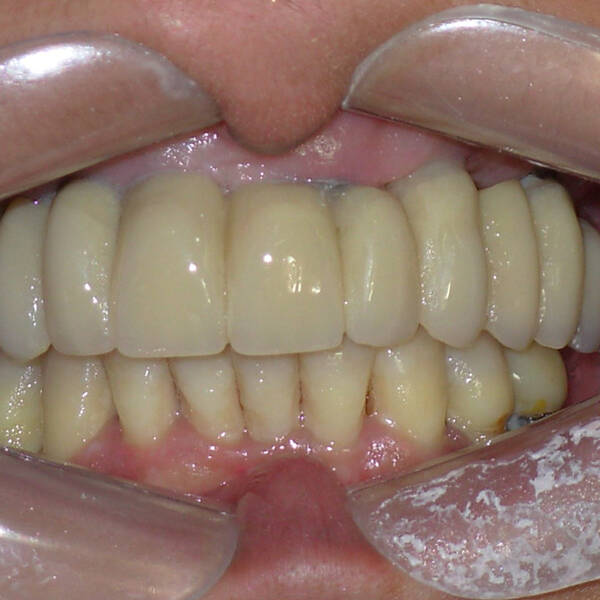

Na Clínica Pontes Odontologia, somos referência em implantes dentários em Fortaleza, oferecendo tratamentos de alta qualidade e tecnologia de ponta. Os implantes dentários são estruturas de titânio posicionadas cirurgicamente no osso maxilar ou mandibular para substituir as raízes dos dentes ausentes. Essa técnica permite a fixação de próteses personalizadas, restaurando a função mastigatória, a estética e a autoestima dos nossos pacientes.

Utilizamos a tecnologia CAD CAM, um sistema avançado que possibilita a confecção precisa das próteses dentárias diretamente sobre os implantes. Esse método inovador garante um ajuste perfeito, um resultado estético superior e proporciona muito mais conforto e durabilidade. Com o CAD CAM, nossos pacientes contam com um processo mais rápido e previsível para alcançar o sorriso desejado.

Nosso compromisso é oferecer um tratamento de excelência, com profissionais especializados e tecnologia de última geração para implantes dentários em Fortaleza. Venha nos visitar e descubra por que a Clínica Pontes Odontologia é referência em implantes dentários em Fortaleza, devolvendo sorrisos e qualidade de vida aos nossos pacientes.